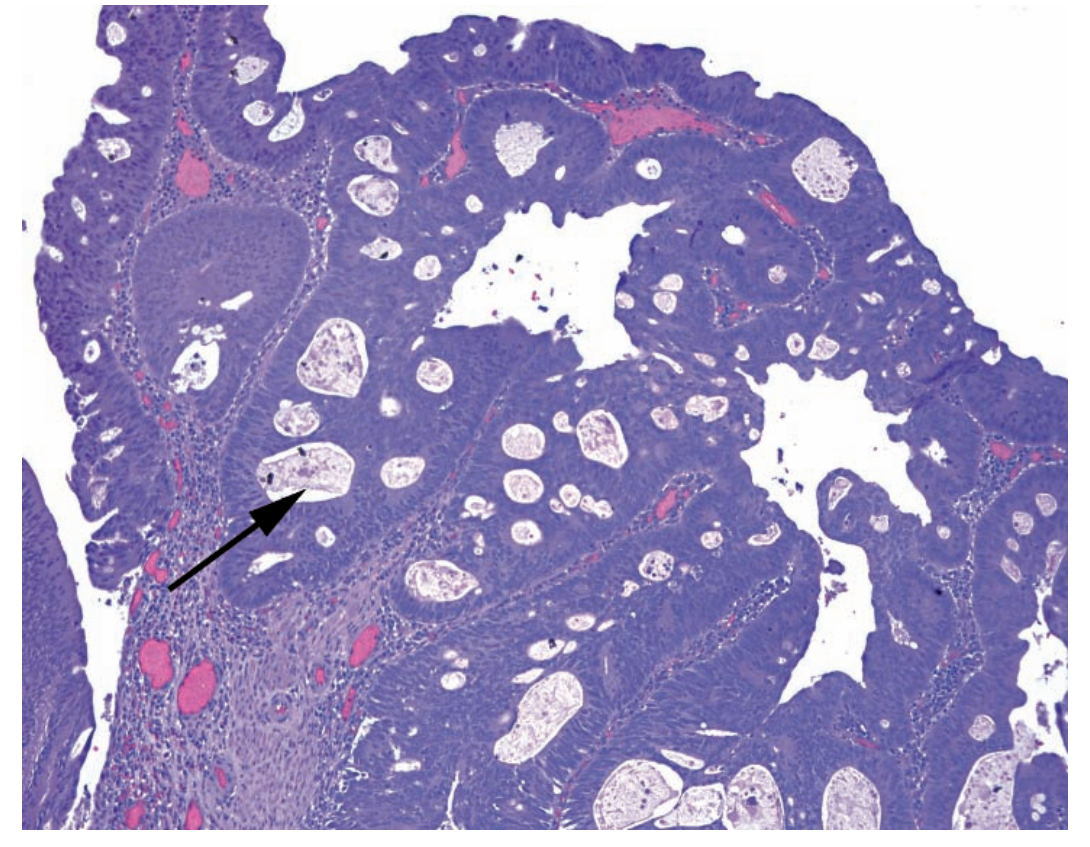

24

A

High-grade dysplasia in an adenoma

Arrow: Cribriforming